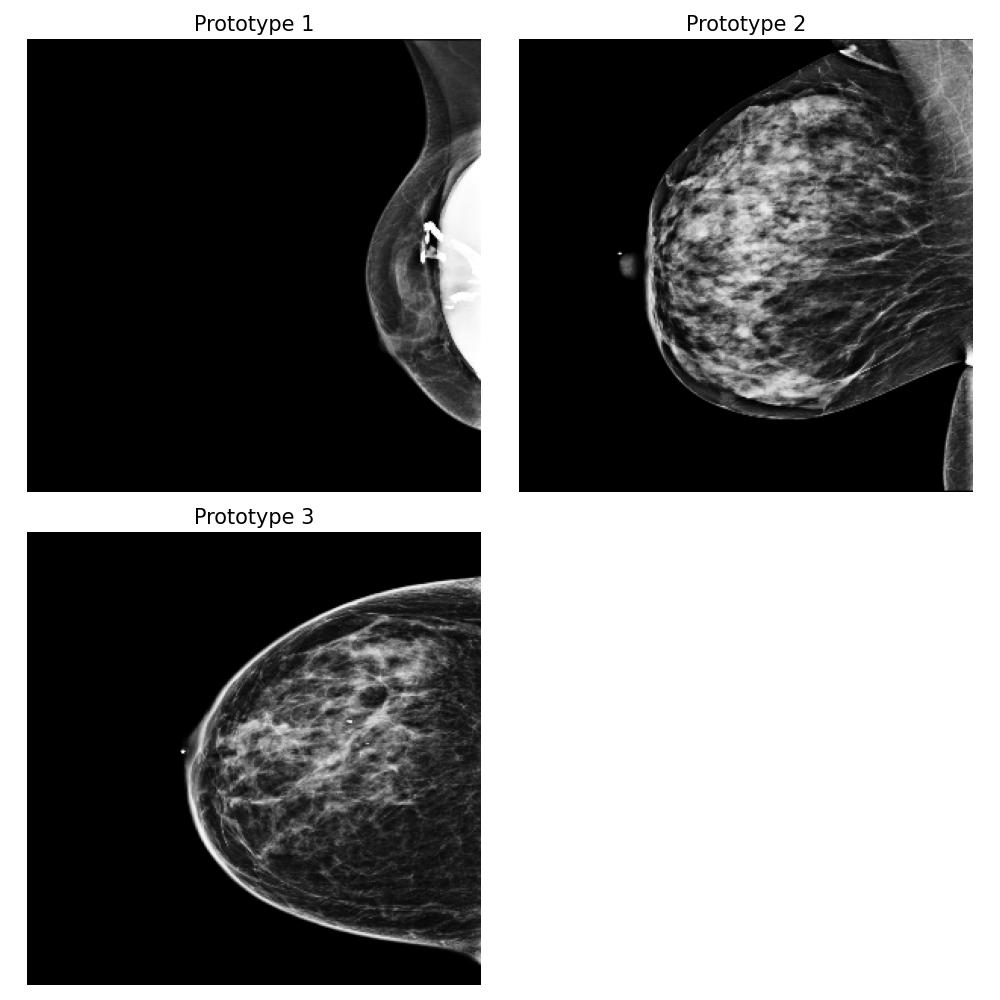

3.5.4 Case Study 2: Medical Image Data - Mammography Patient Population Dataset

In this case study, we assess the effectiveness of our proposed method in a realistic application, focusing on identifying differences between mammograms from two distinct patient populations. Specifically, we simulate a real-world scenario where users deploy models to analyze mammograms of women with varying tissue density distributions — a challenge commonly encountered when comparing premenopausal and postmenopausal patients or younger and older individuals. Premenopausal or younger patients often exhibit denser breast tissue, whereas postmenopausal or older patients often present with less dense tissue (Kim et al., 2020). This dataset evaluation step is crucial before deploying a clinical breast cancer risk detection model across different patient populations.

Dataset and

We use the publicly available EMBED dataset (Jeong et al., 2023). To simulate premenopausal and postmenopausal patient populations, we construct two datasets, and , by randomly sub-sampling from EMBED. Dataset comprises 27,224 mammograms from 8,456 patients with dense breast tissue (density category three in EMBED) and 21,675 mammograms from 7,841 patients in density category two. Dataset includes 27,224 mammograms from 2,715 patients with less dense tissue (density category one) and 21,675 mammograms from 7,797 patients in density category two (medium density). All mammograms were preprocessed to remove clinical markers and aligned such that the breast tissue faces left.

Forming the explanation

For this task, we implemented the “Prototype-summarization-based explanations” described in Section 3.5. We trained a binary vs classifier using the VGG19 feature extractor as backbone and learn four prototypes for each dataset. 97798 mammograms were used for training, and 24450 mammograms were used for testing.

Result

By examining the summarization prototypes shown in Figure 22, we identified tissue density as the primary difference between and . In mammograms, brighter areas correspond to denser tissue. Additionally, we observed that less dense tissue is often associated with larger tissue size. Without our proposed method, human users would need to manually analyze the dataset, which is a labor-intensive and time-consuming task, to reach the same conclusions.

Robustness of the explanation

To examine the robustness of our explanation result, we repeat the explanation algorithm approach on bootstrapped versions of and . Five bootstrapped datasets were constructed by resampling by patients with replacement. As shown in Figure 35 in Appendix Section B.5, we reach the same conclusion for all the bootstrapped datasets.

Coverage evaluation

We again evaluate the coverage quality of the learned set of prototypes using the AUCC score. The coverage curve is shown in Figure 24. We also display the learned latent space for and in Figure 24 and the two datasets and the prototypes are well separated even though they contain overlapping mammograms with density category two (i.e. medium density breasts).